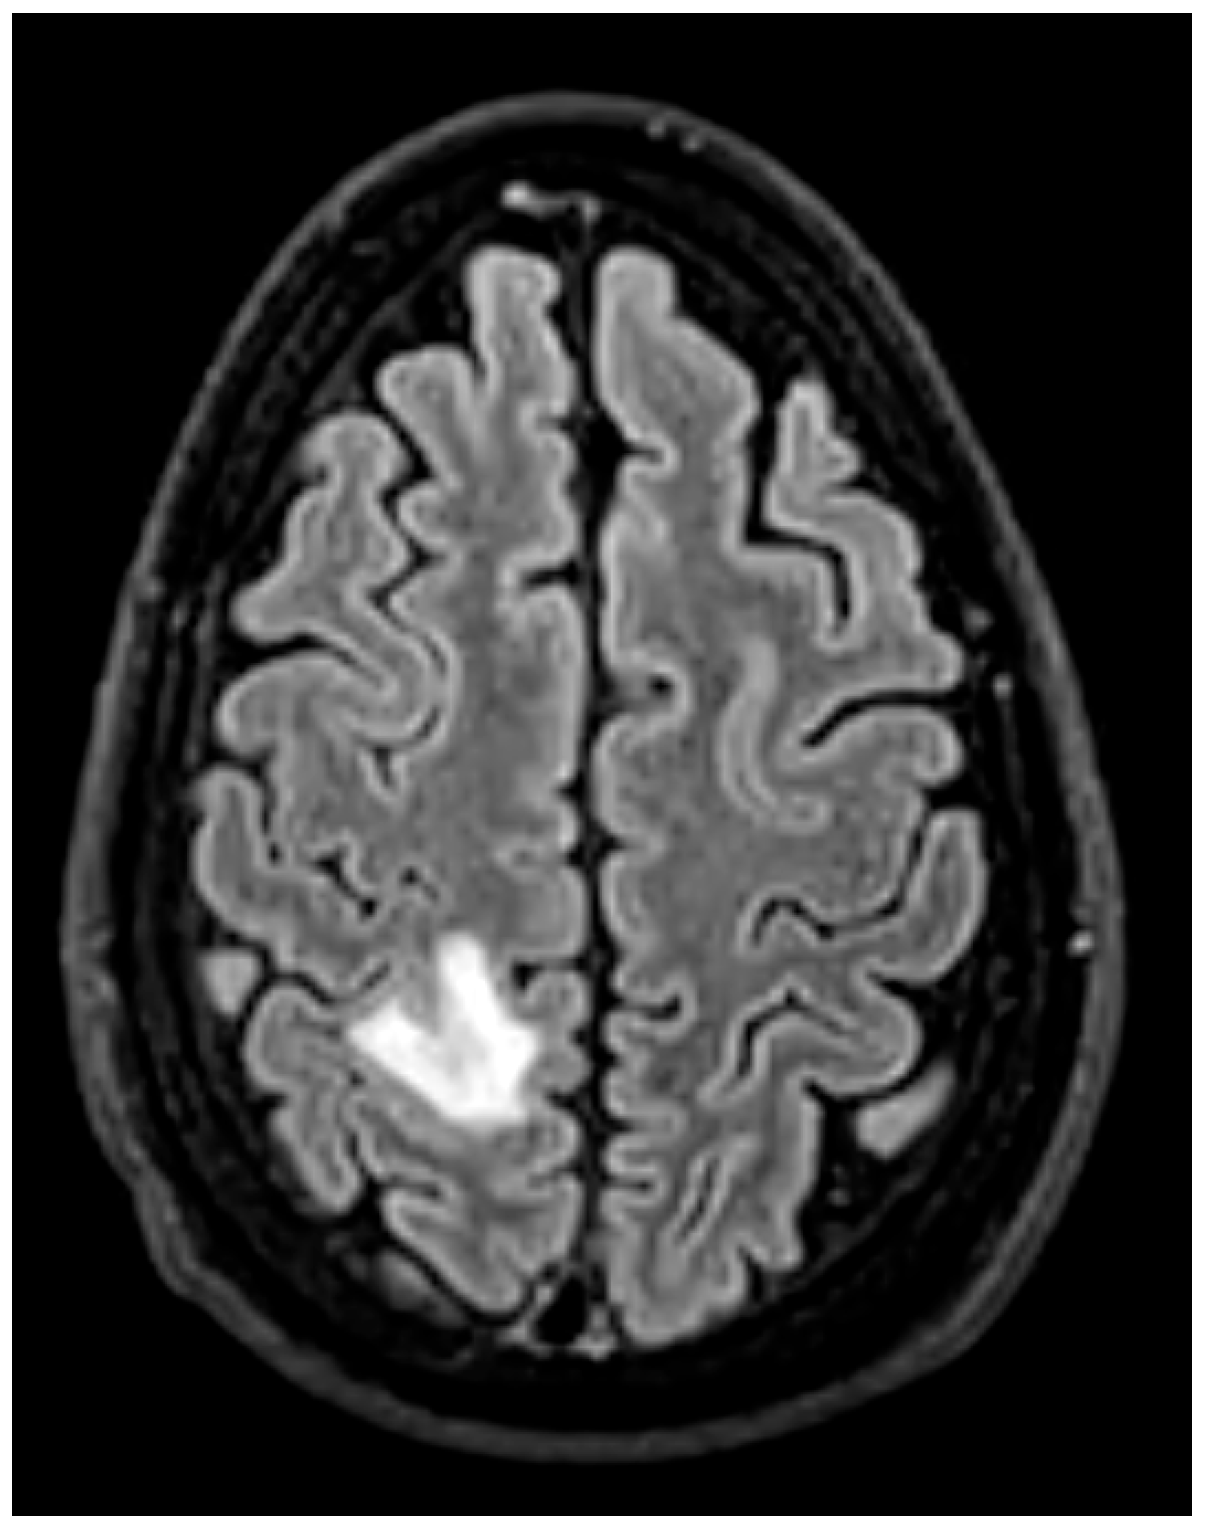

- Brain MRI is especially valuable for identifying clinically occult cerebral emboli, which can influence management decisions and prognosis [24,36] (Figure 15). These occur in 20–40% of IE cases, and a significant portion are clinically silent. Brain MRI with diffusion-weighted imaging (DWI) is the most sensitive modality for detecting acute cerebral infarcts, microabscesses, mycotic aneurysms, and hemorrhages [35,38]. Identifying these findings, even in asymptomatic patients, is critical as it can significantly influence surgical timing and risk stratification. The 2023 ESC guidelines recommend considering brain MRI before cardiac surgery in patients with IE, especially in those with neurological symptoms or high-risk clinical features [13]. For example, the presence of a large cerebral infarct, hemorrhagic lesions, or mycotic aneurysms may prompt delay of valve surgery to reduce the risk of perioperative neurological complications. Conversely, detection of small, non-hemorrhagic embolic lesions may support earlier surgery to prevent further embolization [30]. Prospective data demonstrate that routine cerebral MRI led to changes in surgical plans in up to 14% of cases, including both delays and accelerations of surgery based on neurological risk [39].

- Search for Silent Emboli: A single clinically apparent embolus is often the “tip of the iceberg.” The discovery of one embolic event mandates a systematic search for other, silent emboli, particularly cerebral, which can drastically alter surgical risk and timing. As such, whole-body CT angiography or FDG-PET/CT is recommended to define the full embolic burden [13,39]. Brain MRI is the gold standard for detecting silent cerebral emboli and should be strongly considered before surgery in high-risk patients, even in the absence of neurological symptoms [22].